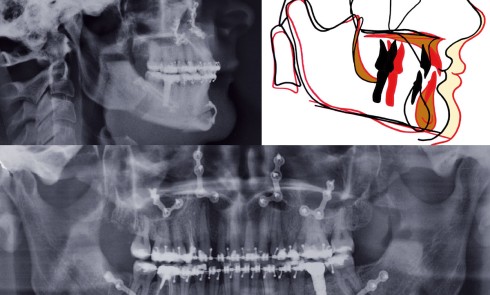

Diagnostic (fig. 1) Cette patiente de 29 ans consulte pour des raisons principalement fonctionnelles mais également esthétiques. Elle présente :– une classe...

ODF